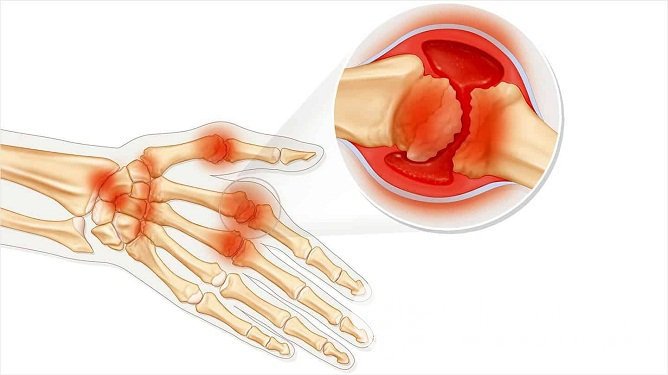

Артрит пальцев рук – одна из самых распространенных форм периферического артрита, при которой воспалительный процесс захватывает пястно-фаланговые и межфаланговые суставы. Первой воспаляется внутренняя синовиальная оболочка сустава, далее патологический процесс распространяется на суставную сумку, хрящи, сухожилия, связки, мышцы и кости.

Артрит пальцев рук – это воспалительный процесс, локализующийся в пястно-фаланговых и межфаланговых суставовПервичный воспалительный процесс обычно развивается на фоне инфекции, ревматической или обменной патологии, реже – на почве перенесенной травмы или хирургического вмешательства. В случае ревматоидного артрита не последнюю роль играет наследственная предрасположенность.

Руки, пораженные артритомЛокализация воспалительного процесса и характер деформаций суставов также имеет важное диагностическое значение. При ревматоидном артрите первые признаки воспаления затрагивают второй и третий пястно-фаланговые суставы и третий проксимальный межфаланговый сустав. Позже патологический процесс распространяется на дистальные межфаланговые суставы, а затем на костно-суставные структуры запястья, а также шиловидный отросток локтевой кости. Поражение суставов обычно носит симметричный характер. На поздних стадиях заболевания наблюдаются характерные деформации кисти: искривления пальцев по типу «бутоньерки» или «лебединой шеи», веретеновидная форма кисти и ульнарные деформации, вызванные частичными вывихами пястно-фаланговых суставов.